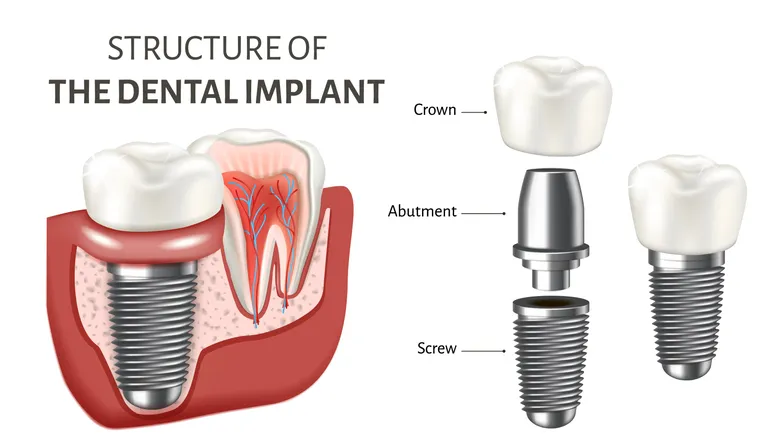

2.2 Components of Dental Implants

2.2.1 Implant Post

The implant post is the primary component of a dental implant. It is a small, screw-like structure made of titanium. The implant post is carefully placed into the jawbone during a minor surgical procedure. The precise positioning ensures proper alignment and stability for the future prosthetic tooth.

The choice of titanium as the material for the implant post is due to its exceptional biocompatibility. Titanium has the unique ability to integrate with bone tissue without causing any adverse reactions. This biocompatibility allows the implant post to become a part of your natural anatomy, providing a strong and secure foundation for the replacement tooth.

2.2.2 Abutment

Once the osseointegration process is complete, the abutment is attached to the implant post. The abutment acts as a connector between the implant post and the prosthetic tooth. It is typically made of titanium or porcelain and is custom-designed to ensure a precise fit.

The abutment serves an essential role in supporting the crown and transferring forces from chewing to the underlying implant post and jawbone. Its position above the gumline allows easy access for the attachment of the final restoration while maintaining gum health and aesthetics.

2.2.3 Crown

The crown is the visible part of the dental implant that resembles a natural tooth. It is custom-made to match the color, shape, and size of your existing teeth, ensuring a seamless and natural appearance. The crown is typically made of high-quality ceramic materials known for their durability and lifelike aesthetics.

To create a crown that blends seamlessly with your natural teeth, detailed impressions, and measurements are taken to ensure an accurate fit and bite. The crown is meticulously crafted by skilled dental technicians using advanced techniques and materials. The result is a prosthetic tooth that replicates the characteristics of your natural teeth, including color, texture, and translucency.